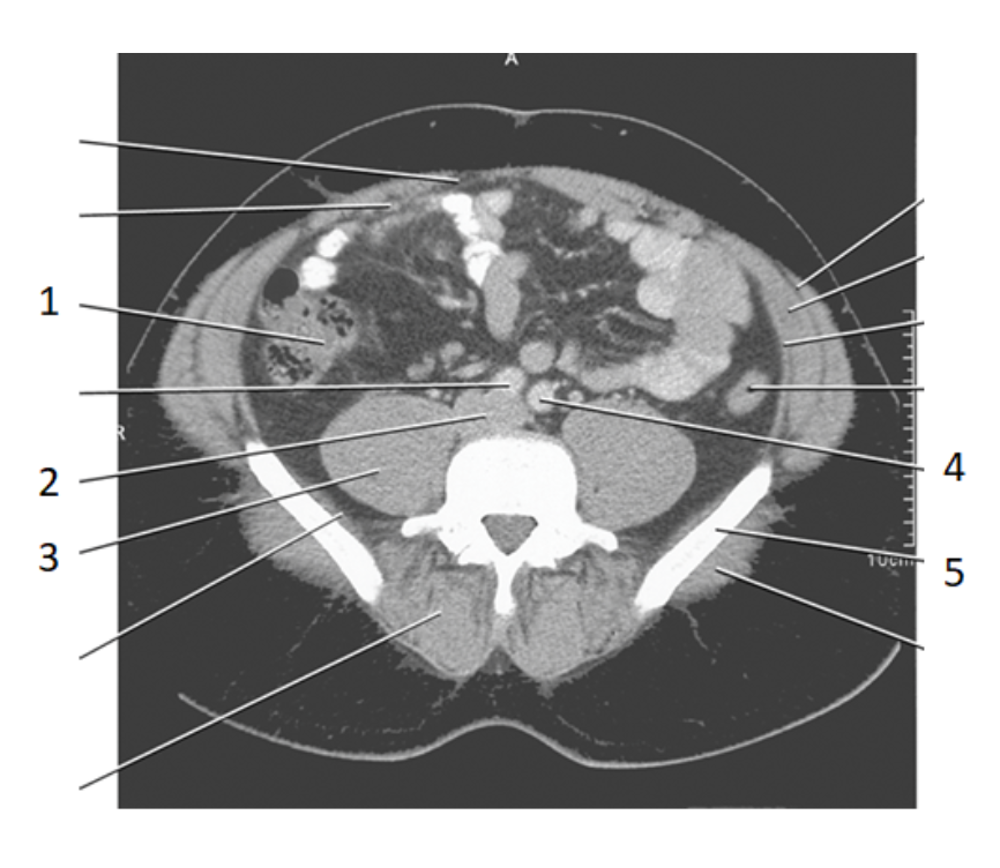

2

aorta

4

left common iliac artery

3

ureters

8

psoas

24